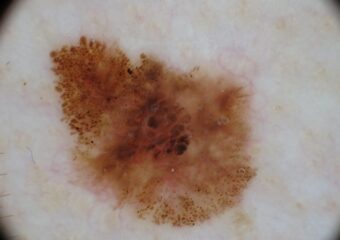

Basal Cell Carcinoma (BCC) Photos

Basal cell carcinoma on the posterior torso. Photo: International Skin Imaging Collaboration at isic-archive.com

Basal cell carcinoma on the neck. Photo: International Skin Imaging Collaboration at isic-archive.com

Basal cell carcinoma on the anterior torso. Photo: International Skin Imaging Collaboration at isic-archive.com

Basal cell carcinoma on the anterior torso. Photo: International Skin Imaging Collaboration at isic-archive.com

Basal cell carcinoma on the anterior torso. Photo: International Skin Imaging Collaboration at isic-archive.com